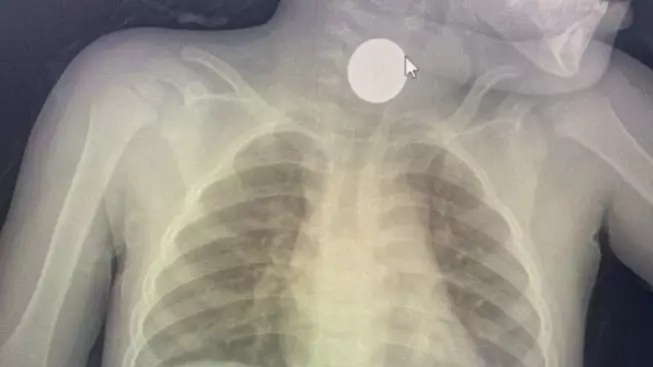

Жамбыл облысында дәрігер 3 жасар баланың өңешінен 100 теңгені алып шықты

Жамбыл облысы Байзақ аудандық орталық ауруханасының дәрігері өңешіне тиын тұрып қалған баланы аман алып қалды. 3 жасар бала абайсызда 100 теңгелік тиынды жұтып қойған.